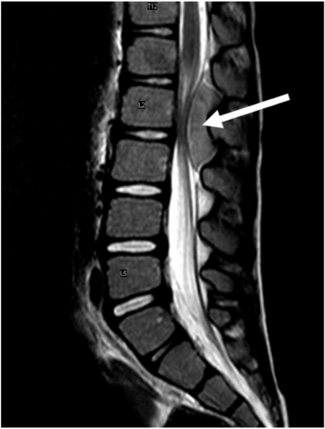

神经母细胞瘤肿块压迫脊髓的患者脊柱MRI,箭头指示处为肿瘤肿块。